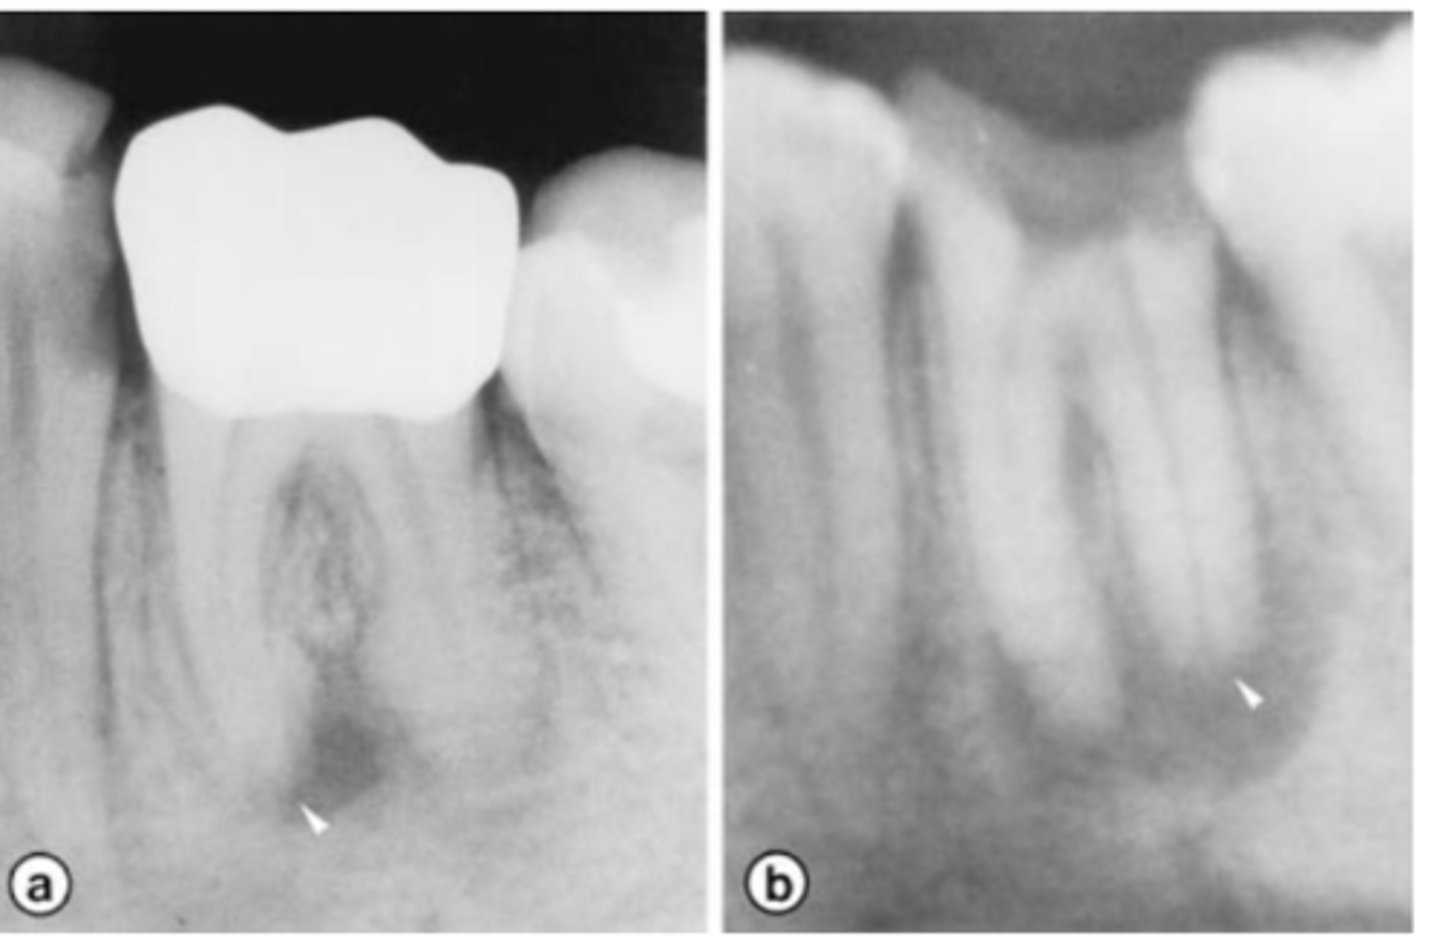

Internal inflammatory resorption

What is the diagnosis?

- Usually asymptomatic and have a normal appearance

- May have pink/red spot on the crown due to granulation tissue in the coronal dentin

- May display signs of pulpitis:

+ to sensibility tests in (partially) vital cases

- to sensibility tests in necrotic cases

- Symmetrical ballooning of root canal

- Lesion does not move when PA is taken from different angles

- Usually does not have periapical lesion (Apical portion of root is vital!)

- Lesion may perforate into alveolar bone

- CBCT is recommended

Patient presents asymptomatic with a normal appearance but there is a pink/red spot on the tooth, what is the most likely diagnosis?

Patient presents with symmetrical ballooning of the root canal and lesion does not move when PA is taken from different angles. There is no PARL. What is the most likely diagnosis?